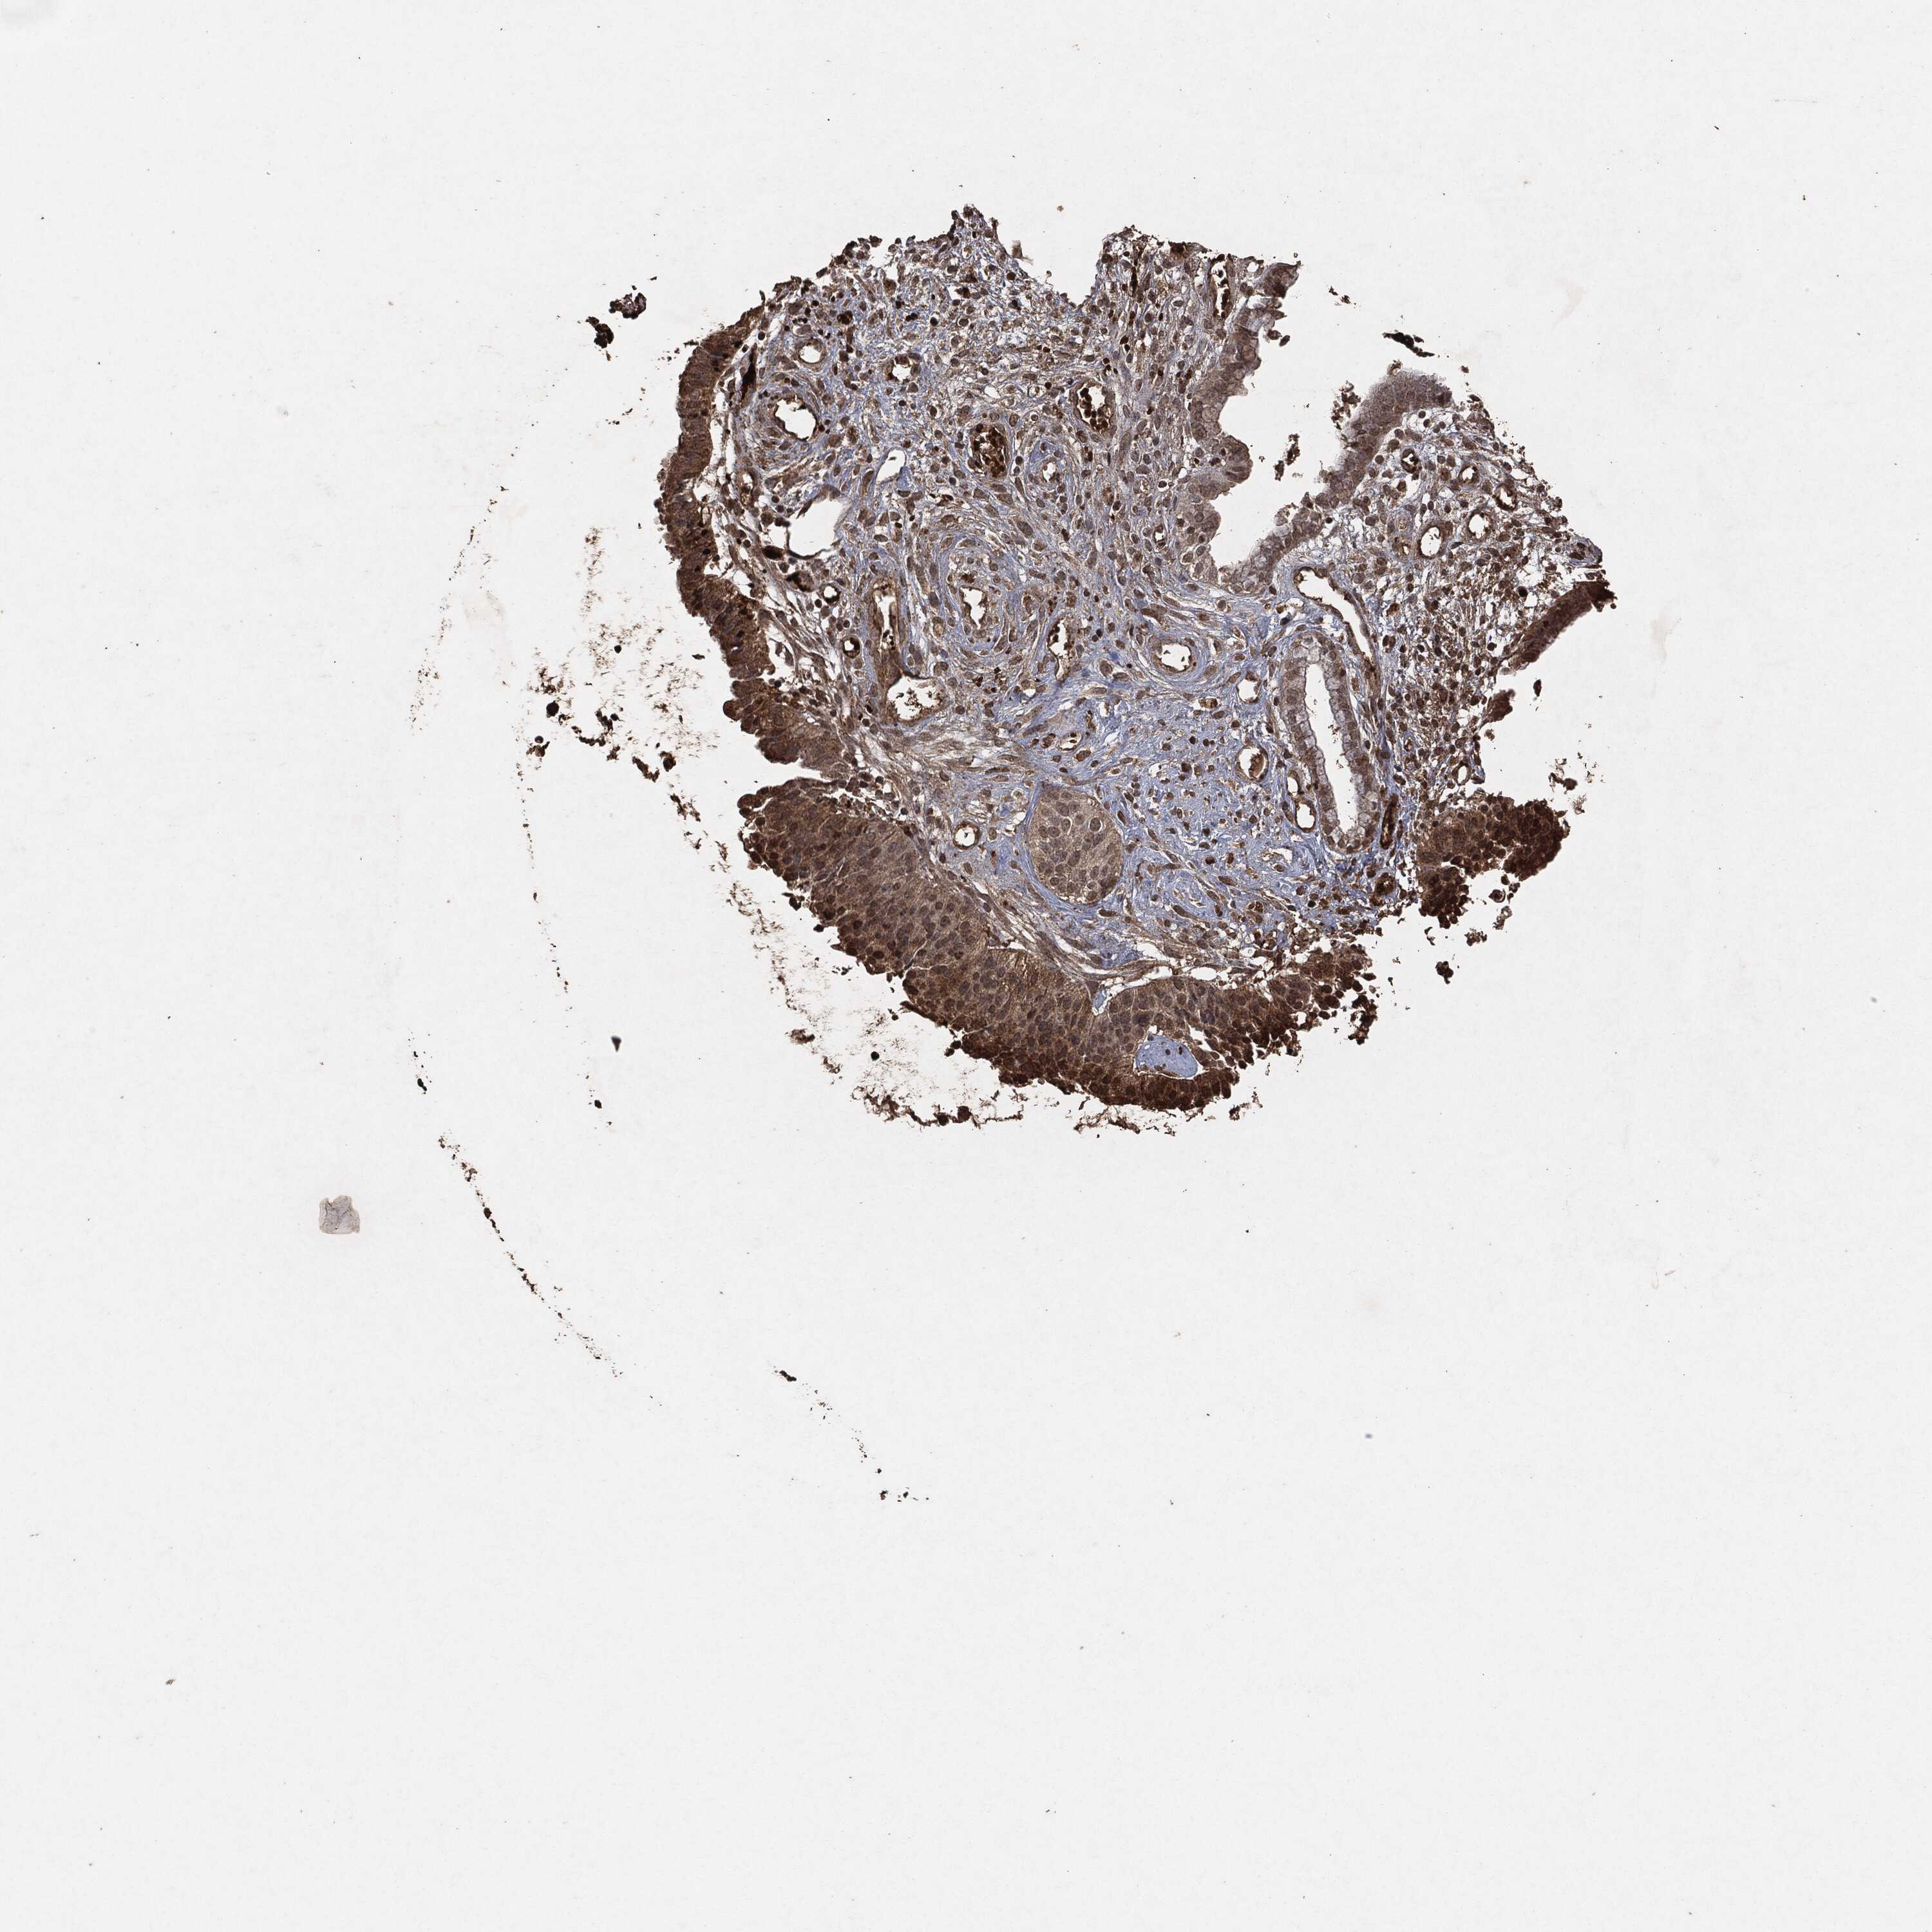

CERVICAL CANCER - Protein expressioni

A mouse-over function shows sample information and annotation data. Click on an image to view it in a full screen mode. Samples can be filtered based on level of antibody staining by selecting one or several of the following categories: high, medium, low and not detected. The assay and annotation is described here.

Note that samples used for immunohistochemistry by the Human Protein Atlas do not correspond to samples in the TCGA dataset.

Antibody stainingi

Antibody staining in the annotated cell types in the current human tissue is reported as not detected, low, medium, or high, based on conventional immunohistochemistry profiling in selected tissues. This score is based on the combination of the staining intensity and fraction of stained cells.

Each image is clickable and will lead to virtual microscopy that enables deeper exploration of all samples and also displays staining intensity scores, fraction scores and subcellular localization as well as patient and tissue information for each sample.

Staining

High

Medium

Low

Not detected

Intensity

Strong

Moderate

Weak

Negative

Quantity

>75%

75%-25%

<25%

None

Location

Nuclear

Cytoplasmic/membranous

Cytoplasmic/membranous,nuclear

Adenocarcinoma, NOS

Squamous cell carcinoma, NOS